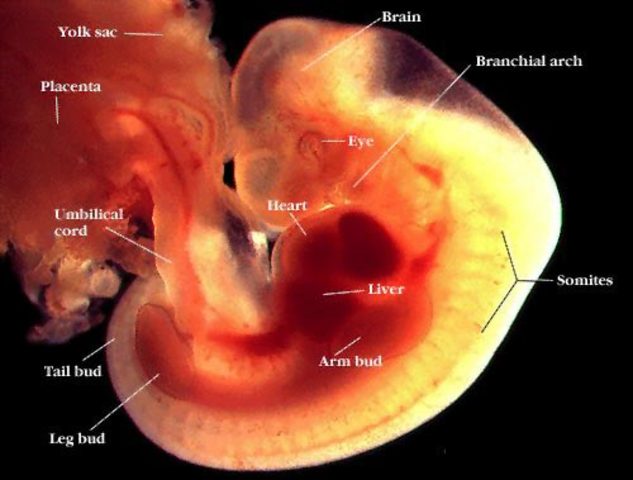

• Weeks 1-6 development

Weeks 1-6 development

the brain and spinal cord are developing over three and four weeks after the last menstrual cycle. The five weeks after the last menstural cycle is when the zygote is developing the brain, neural tube, it is also developing three layers( ectoderm, mesoderm, endoderm.) by week 6 the neural tube is closed.By this time the baby is the size of the tip of a pen.